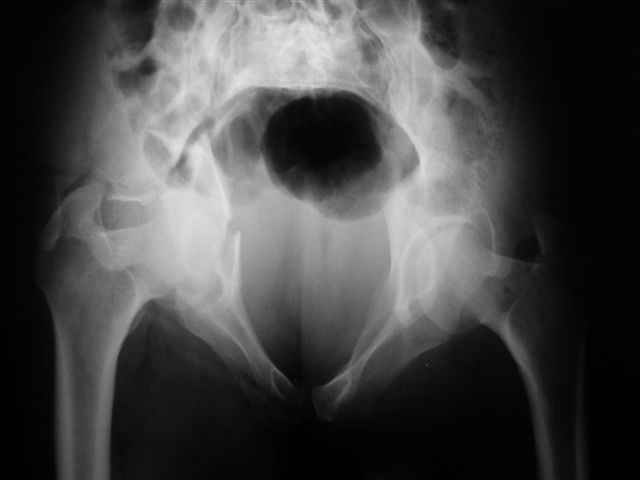

Уважаемые коллеги,43 летний мужчина, попав в автоаварию 13.10.2004, получил оскольчатый перелом обеих колонн левой вертлужной впадины.

На рентгенограммах - высокий двухколонный перелом вертлужной впадины с нарушением конгруэнтности, имеется обратная клиновидность суставной щели.